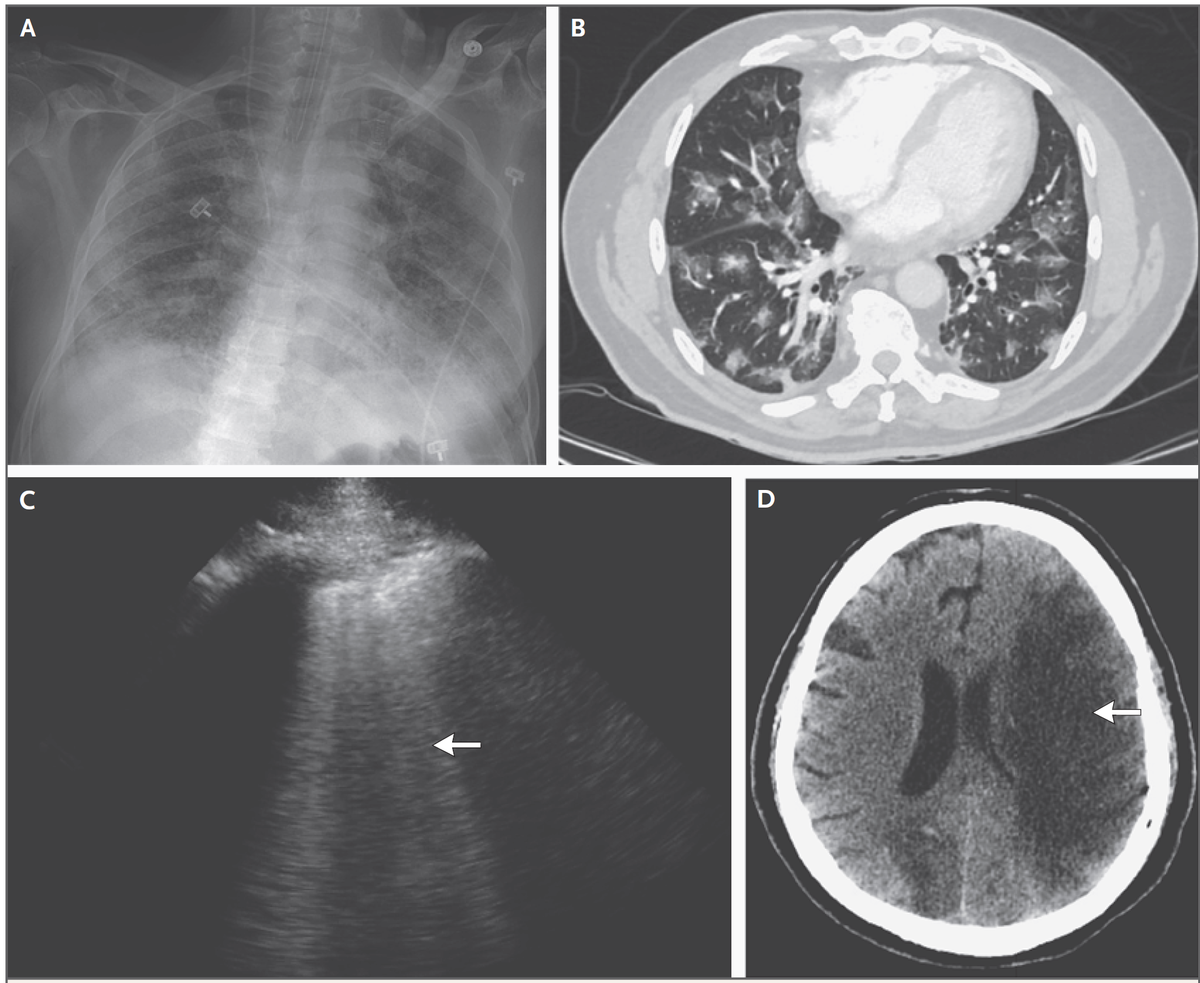

・胸部画像検査では両側性のconsolidationやすりガラス影が典型的

A)胸部レントゲン…両側性のすりガラス影と浸潤影

B)胸部CT…両側すりガラス影

C)経胸壁超音波…B line

D)頭部CT…脳塞栓症